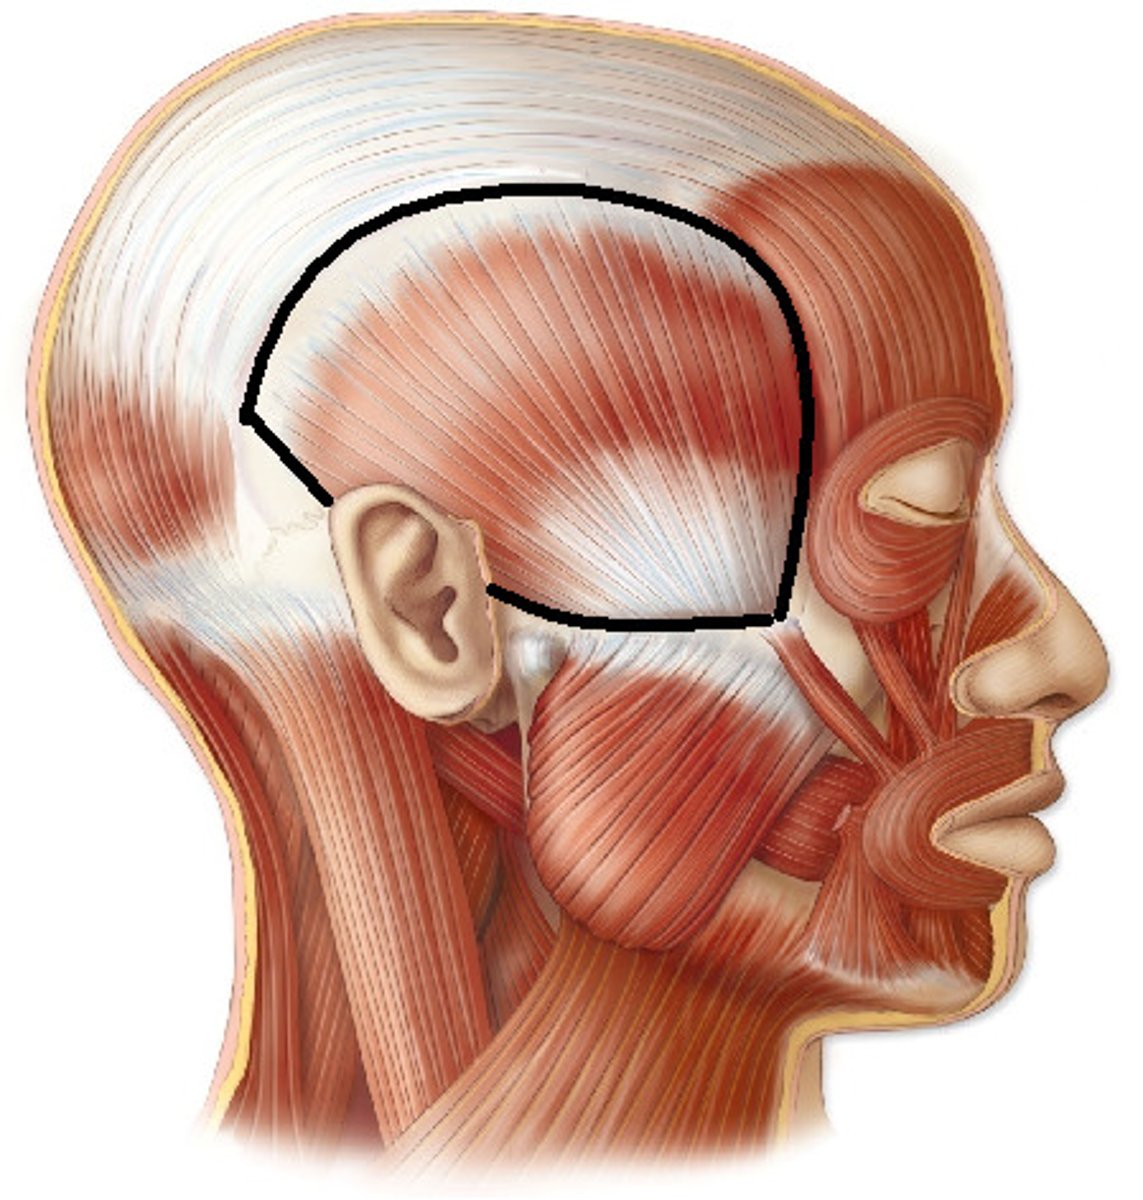

Temporalis

A broad, fan-shaped muscle on each side of the head that fills the temporal fossa, superior to the zygomatic arch so it covers much of the temporal bone